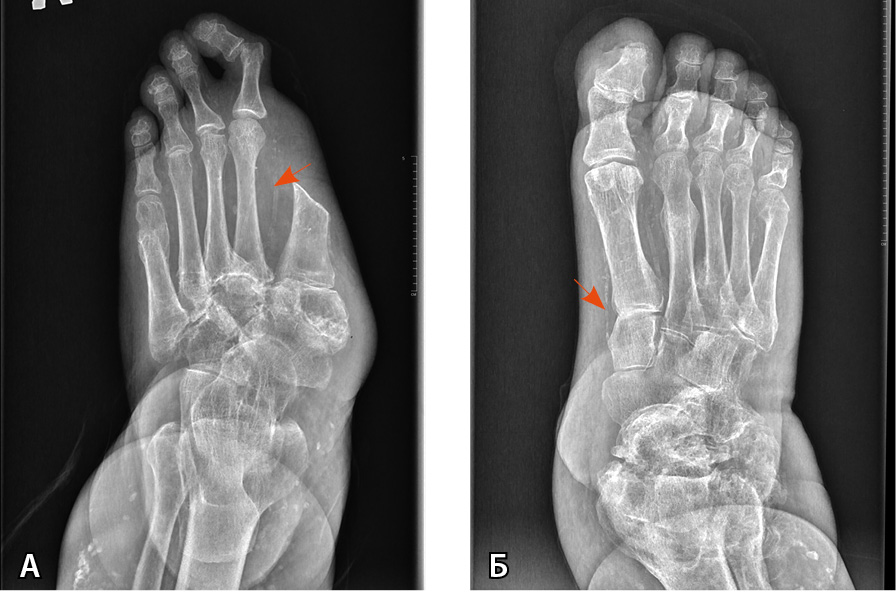

Рис. 3. Рентгенограмма обеих стоп пациента Т. в прямой проекции (стрелками указаны кальцинированные сосуды):

А – артропатическая перестройка структуры костей предплюсны, переломы на уровне оснований 3–5-й плюсневых костей с признаками консолидации. Консолидированный перелом головки 5-й плюсневой кости. Ампутация I пальца;

Б – артропатическая перестройка структуры костей предплюсны и правого голеностопного сустава, консолидированные переломы II, III, V пальцев. Остеомиелит ногтевой фаланги I пальца